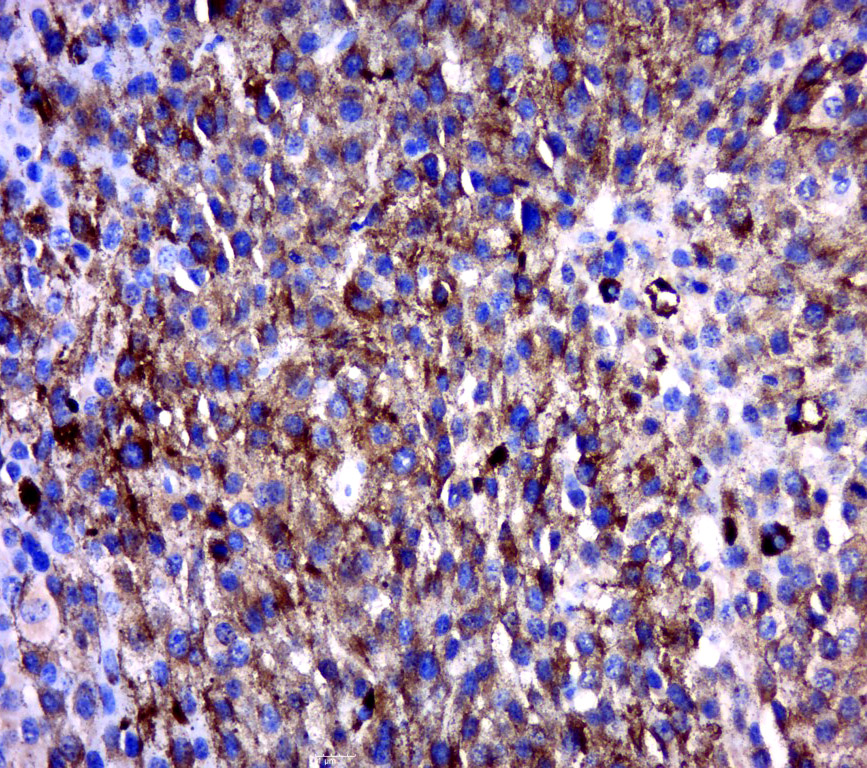

Immunohistochemical staining of human testis shows strong cytoplasmic positivity in subset of cells of seminiferus ducts.